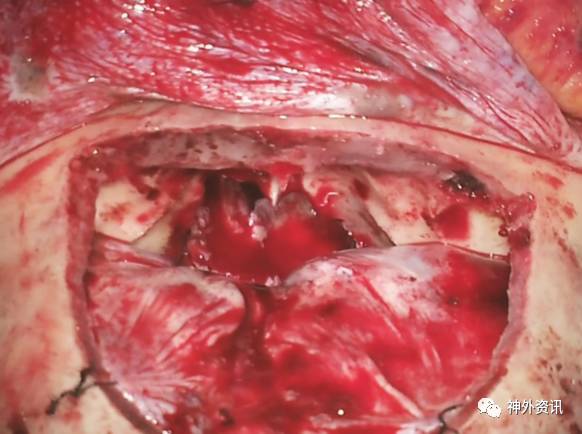

图10. 利用吸引器对额叶实现动态牵拉。将嗅球进行锐性分离,暴露硬膜外扩展的肿瘤前部(星形)。术中图像展示的是一侵犯鼻腔的前颅底软骨肉瘤切除术(上文图1)。锐性分离嗅球直接造成硬膜敞开并且显露肿瘤的硬膜内部分。